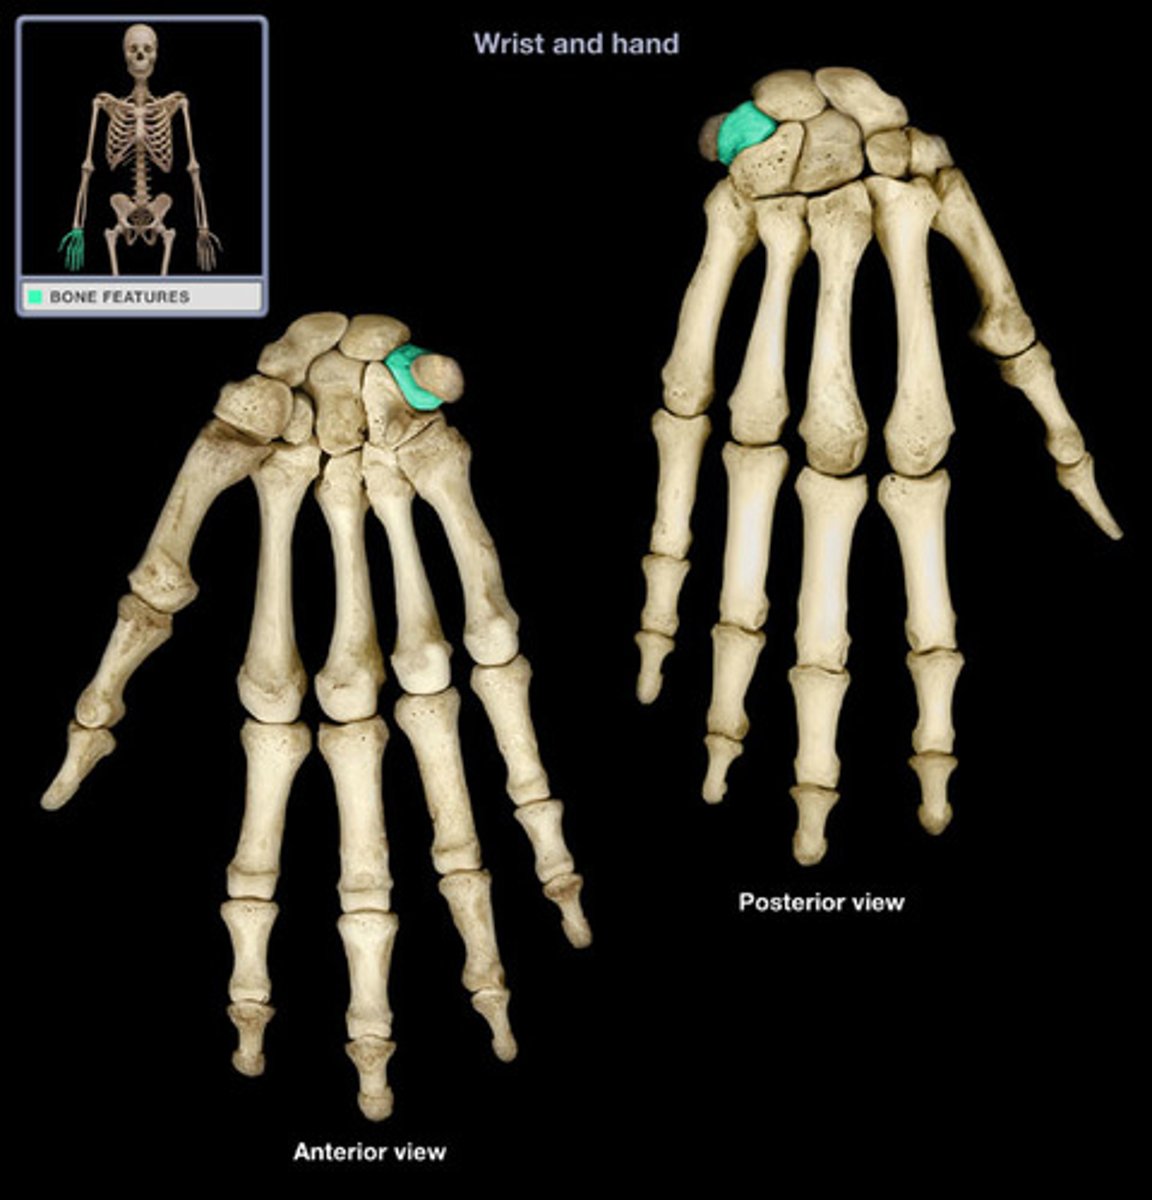

Carpal bones

scaphoid, lunate, triquetrum, pisiform, trapezium, trapezoid, capitate, hamate

Lunate

Name this specific bone of the hand.

Triquetrum

Name this specific bone of the hand.

Pisiform

Name this specific bone of the hand.

Trapezium

Name this specific bone of the hand.

Trapezoid

Name this specific bone of the hand.

Capitate

Name this specific bone of the hand.

Hamate

Name this specific bone of the hand.